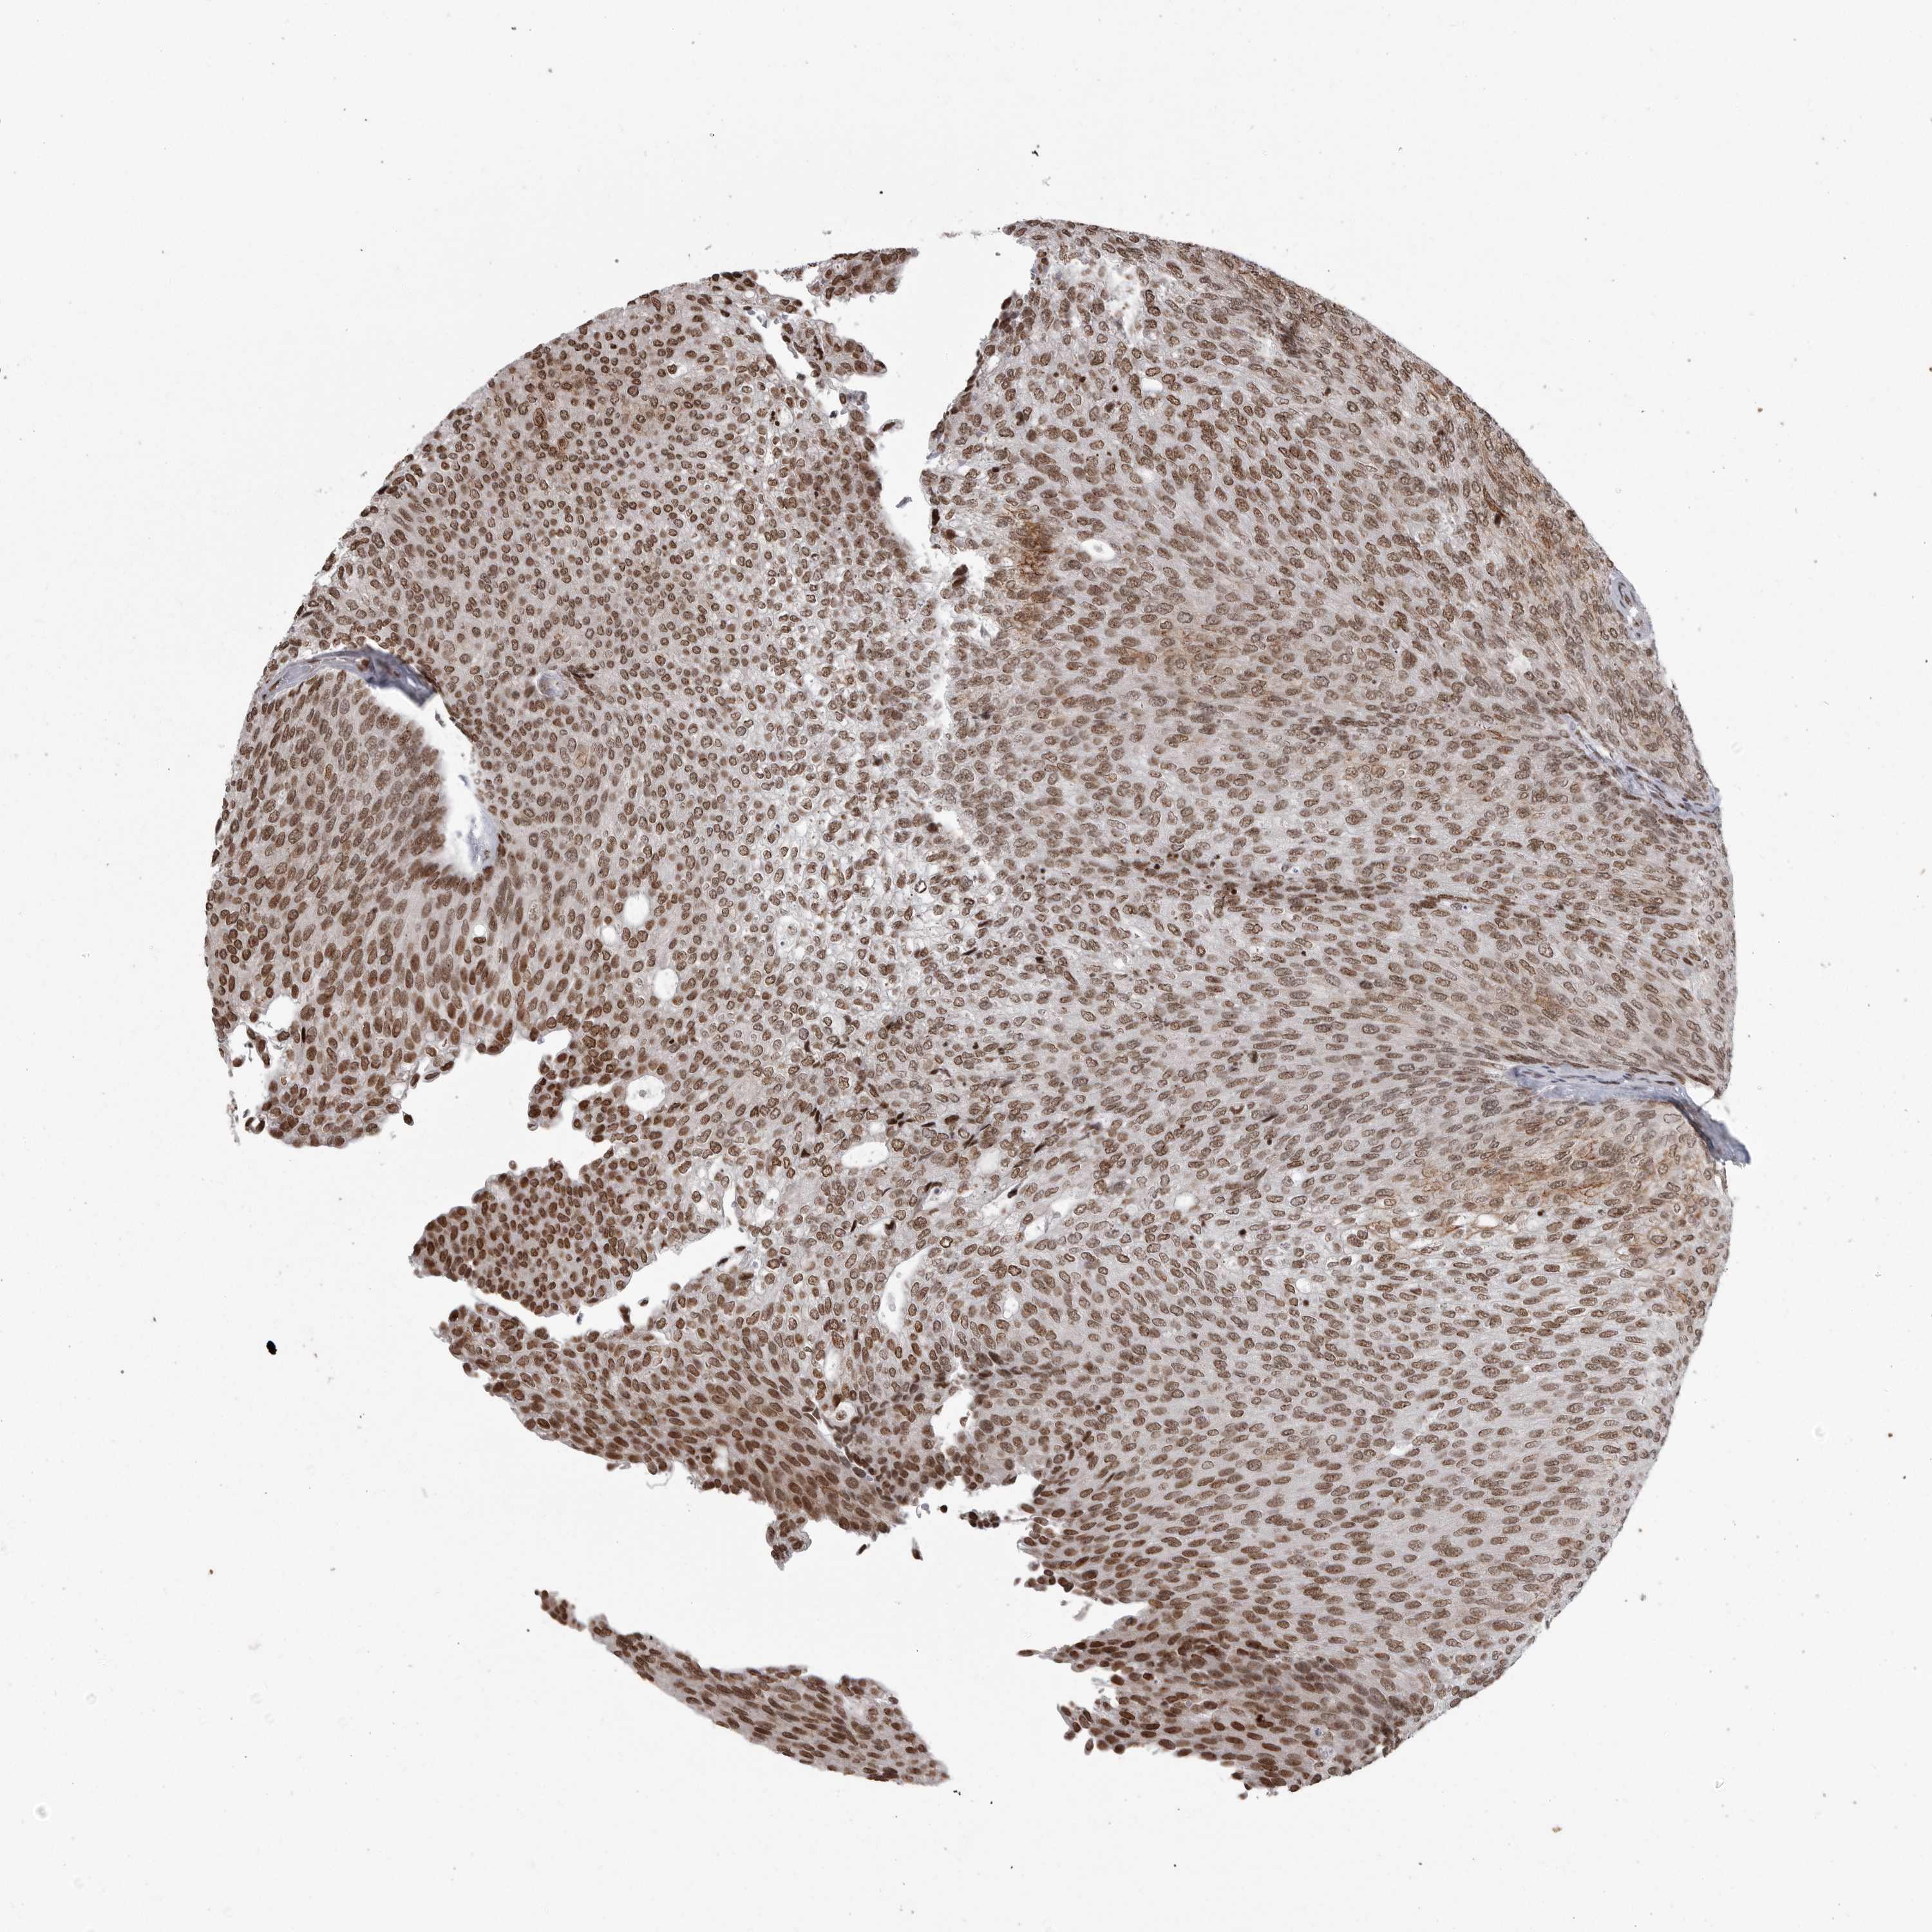

UROTHELIAL CANCER - Protein expressioni

A mouse-over function shows sample information and annotation data. Click on an image to view it in a full screen mode. Samples can be filtered based on level of antibody staining by selecting one or several of the following categories: high, medium, low and not detected. The assay and annotation is described here.

Antibody stainingi

Antibody staining in the annotated cell types in the current human tissue is reported as not detected, low, medium, or high, based on conventional immunohistochemistry profiling in selected tissues. This score is based on the combination of the staining intensity and fraction of stained cells.

Each image is clickable and will lead to virtual microscopy that enables deeper exploration of all samples and also displays staining intensity scores, fraction scores and subcellular localization as well as patient and tissue information for each sample.

Antibody HPA026867

Staining

High

Medium

Low

Not detected

Intensity

Strong

Moderate

Weak

Negative

Quantity

>75%

75%-25%

<25%

None

Location

Nuclear

Cytoplasmic/membranous

Cytoplasmic/membranous,nuclear

Urothelial carcinoma, Low grade

Urothelial carcinoma, High grade